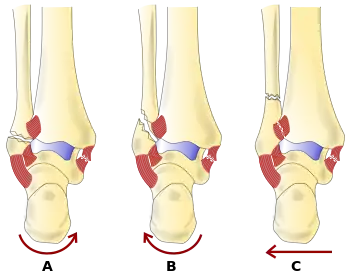

The Danis–Weber classification (often known just as the Weber classification) is a method of describing ankle fractures. It has three categories:[1]

- Type A

Fracture of the fibula distal to the syndesmosis (the connection between the distal ends of the tibia and fibula). Typical features:

- below level of the ankle joint

- tibiofibular syndesmosis intact

- deltoid ligament intact

- medial malleolus occasionally fractured

- usually stable: occasionally nonetheless requires an open reduction and internal fixation (ORIF) particularly if medial malleolus fractured

- Type B

Fracture of the fibula at the level of the syndesmosis. Typical features:

- at the level of the ankle joint, extending superiorly and laterally up the fibula

- tibiofibular syndesmosis intact or only partially torn, but no widening of the distal tibiofibular articulation

- medial malleolus may be fractured or deltoid ligament may be torn

- variable stability

- Type C

Fracture of the fibula proximal to the syndesmosis. Typical features:

- above the level of the ankle joint

- tibiofibular syndesmosis disrupted with widening of the distal tibiofibular articulation

- medial malleolus fracture or deltoid ligament injury present

- unstable: requires ORIF

Categories B and C imply a degree of damage to the syndesmosis itself (which cannot be directly visualised on X-ray). They are inherently unstable and are more likely to require operative repair to achieve a good outcome. Type A fractures are usually stable and can be managed with simple measures, such as a plaster of paris cast.